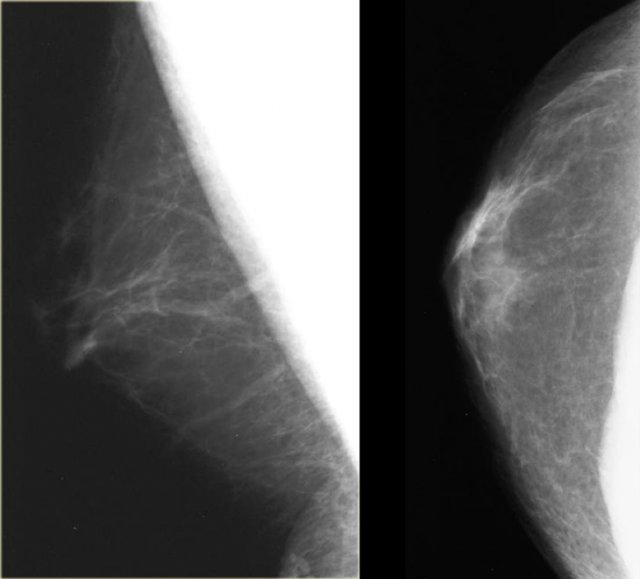

Ngoài cùng bên trái là nhũ ảnh của một nam giới bị gynecomastia và bên cạnh là nhũ ảnh của một bé gái tám tuổi bị phì đại vú tuổi thiếu niên.

Lưu ý rằng hai hình ảnh này trông rất giống nhau.